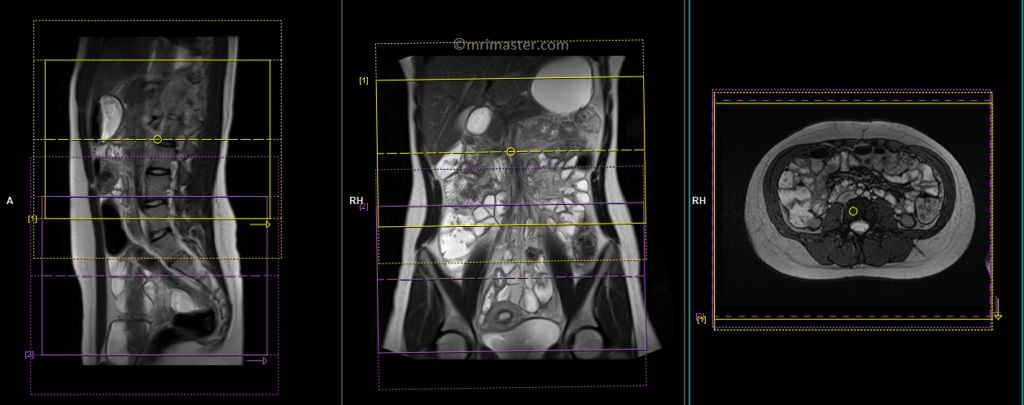

T1 VIBE DIXON \ flash fat sat 3d 0.9-1 mm coronal pre-contrast

Plan the coronal slices on the axial image. Position the block horizontally across the abdomen as shown, and ensure that the positioning block is also checked in the other two planes. Establish an appropriate angle vertically across the abdomen in the sagittal plane. Make sure the slices adequately cover the entire abdomen, extending from the anterior abdominal wall to the erector spinae muscle. The field of view (FOV) should be large enough to encompass the abdomen and pelvis, ranging from the stomach to the pubic symphysis. To prevent wrap-around artifacts, phase oversampling, and in the case of 3D blocks, slice oversampling must be used. Instruct the patient to hold their breath during image acquisition. (In our department, we instruct the patients to breathe in and out twice before giving the “breathe in and hold” instruction.)

Protocol Parameters T1 FLASH Coronal

TR 3-4 | TE 1-2 | FLIP 12 | NEX 1 | SLICE 1 MM | MATRIX 384X320 | FOV 400-450 | PHASE R>L | OVERSAMPLE 50% | IPAT OFF |